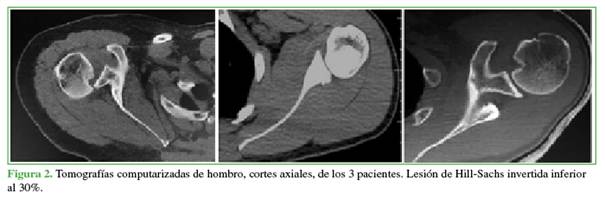

Los criterios de inclusión fueron: luxaciones agudas reducidas en la Guardia, tratamiento de la inestabilidad dentro de la segunda y tercera semana del episodio, lesión de Bankart invertida, lesión de Hill-Sachs invertida que comprometiera hasta el 30% de la cabeza humeral (Figuras 1 y 2).